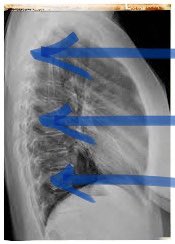

A CXR only captures an image in 2D. The radiographic findings of a pneumothorax may be subtle or atypical. A #pneumothorax may not be visible if you still have an expanded lung present in the field of where the CXR imaging was taken. See image below:

A CXR only captures an image in 2D. The radiographic findings of a pneumothorax may be subtle or atypical. A #pneumothorax may not be visible if you still have an expanded lung present in the field of where the CXR imaging was taken. See image below: